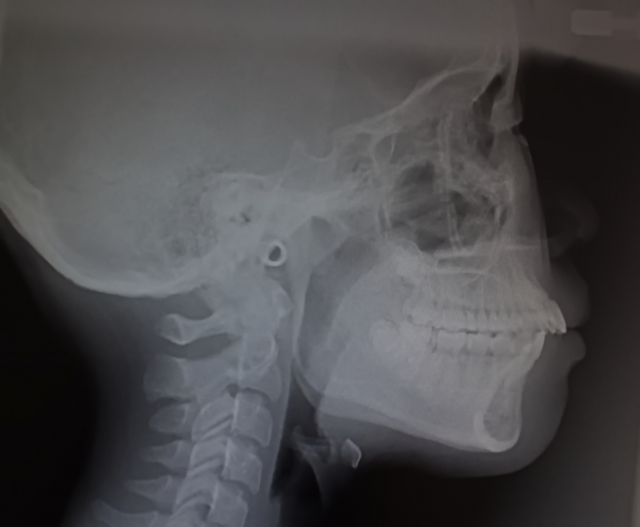

セファロ分析による骨格診断

正中ずれの真の原因が歯性なのか骨格性なのかを正確に診断するためには、頭部X線規格写真を用いたセファロ分析が必要です。これにより、顎の骨格的なバランスや上顎と下顎の位置関係を数値で客観的に評価ができます。

・レントゲン写真

・セファログラム